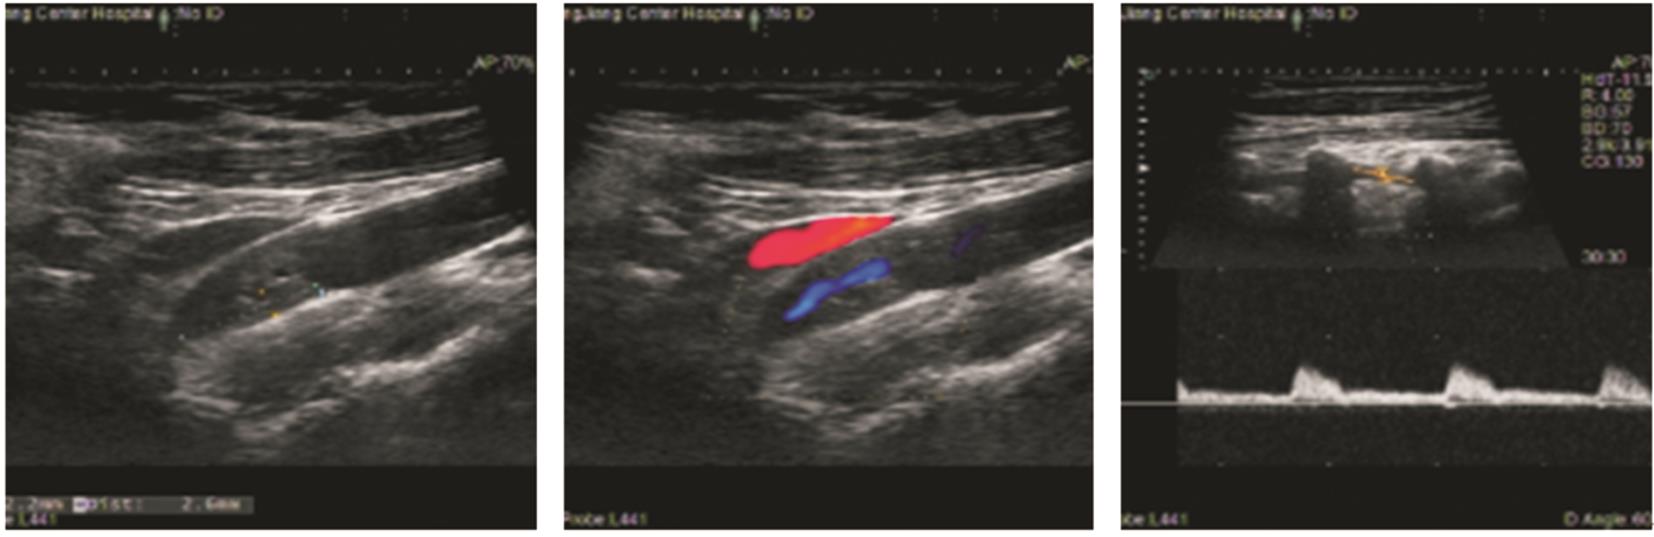

摘要:该文追踪1例低叶酸血症患者6年,观察患者体内血栓的动态演变过程。对该例患者进行了叶酸水平、同型半胱氨酸、维生素B12水平监测,同时监测患者的颈动脉超声、下肢动脉超声、头颅磁共振成像和磁共振血管成像,并获得患者的基因学检测结果。第1年,患者出现了左侧大脑中动脉皮质支闭塞(叶酸2.23 ng/mL)。第2年,患者出现了左下肢深静脉血栓(叶酸2.58 ng/mL)。第3年,患者出现左侧颈内动脉颅内段大部分闭塞(叶酸2.16 ng/mL)。第4年,患者出现右下肢深静脉血栓+左侧颈内动脉颅外段狭窄+右下肺静脉血栓形成(叶酸2.27 ng/mL),此时启动了补充叶酸治疗。第5年,患者未再新发血栓。采用DNA微阵列法检测发现,该例患者基因组中MTHFR基因677位为T/T纯合型(突变型)。第6年,患者死于肺炎。该类型突变的患者会出现低叶酸血症,导致快速侵袭性、全身动静脉多发性血栓,补充叶酸治疗可能有效。